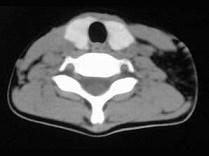

问题 女,17岁,发现左侧颈部包块半年余,PE:病灶质软,境界不清,无压痛,CT如图所示,应诊断为 ( )

选项 A、颈部淋巴管瘤 B、颈部陈旧性血肿 C、颈部畸胎瘤 D、颈部错构瘤 E、颈部脂肪瘤

答案 E